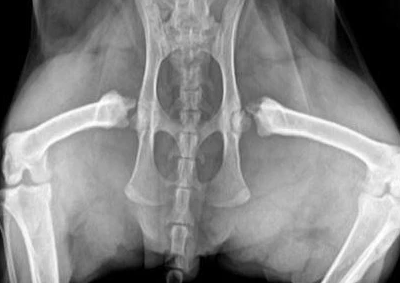

Thoracic radiology is an essential part of veterinary practice but the interpretation of thoracic radiographs often leads to anxiety amongst veterinarians. This presentation will review the pulmonary parenchymal changes that occur with disease using a distribution and pattern based approach. Certain pulmonary diseases characteristically occur in the cranioventral or caudodorsal regions of the lungs. Integrating this knowledge, with the identification of the pulmonary pattern present, aids the construction of a logical ranked order list of differential diagnoses. The sometimes hazy, shadowy world of thoracic radiology will be demystified and made sense of with this practical approach to interpretation. Clinical case examples will be used to demonstrate how this approach with the aim of making reading thoracic radiographs a rewarding part of veterinary practice.